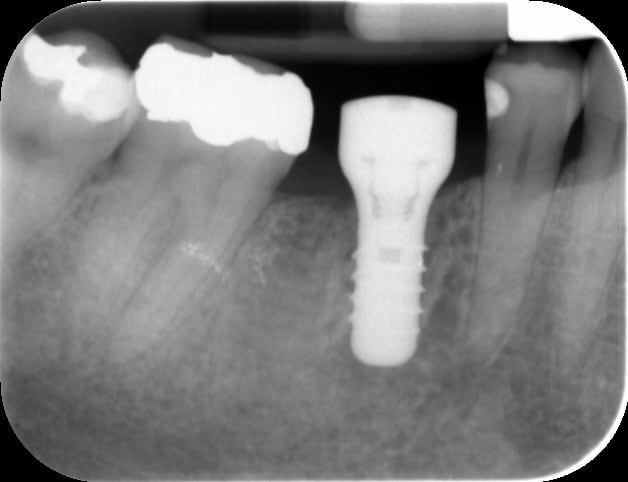

Il y a 2 semaines j'ai posé un implant de 46 tout simple, sans aucune complication.

- 46 ne présente aucune suppuration, bon son de l"implant, RAS à la radio